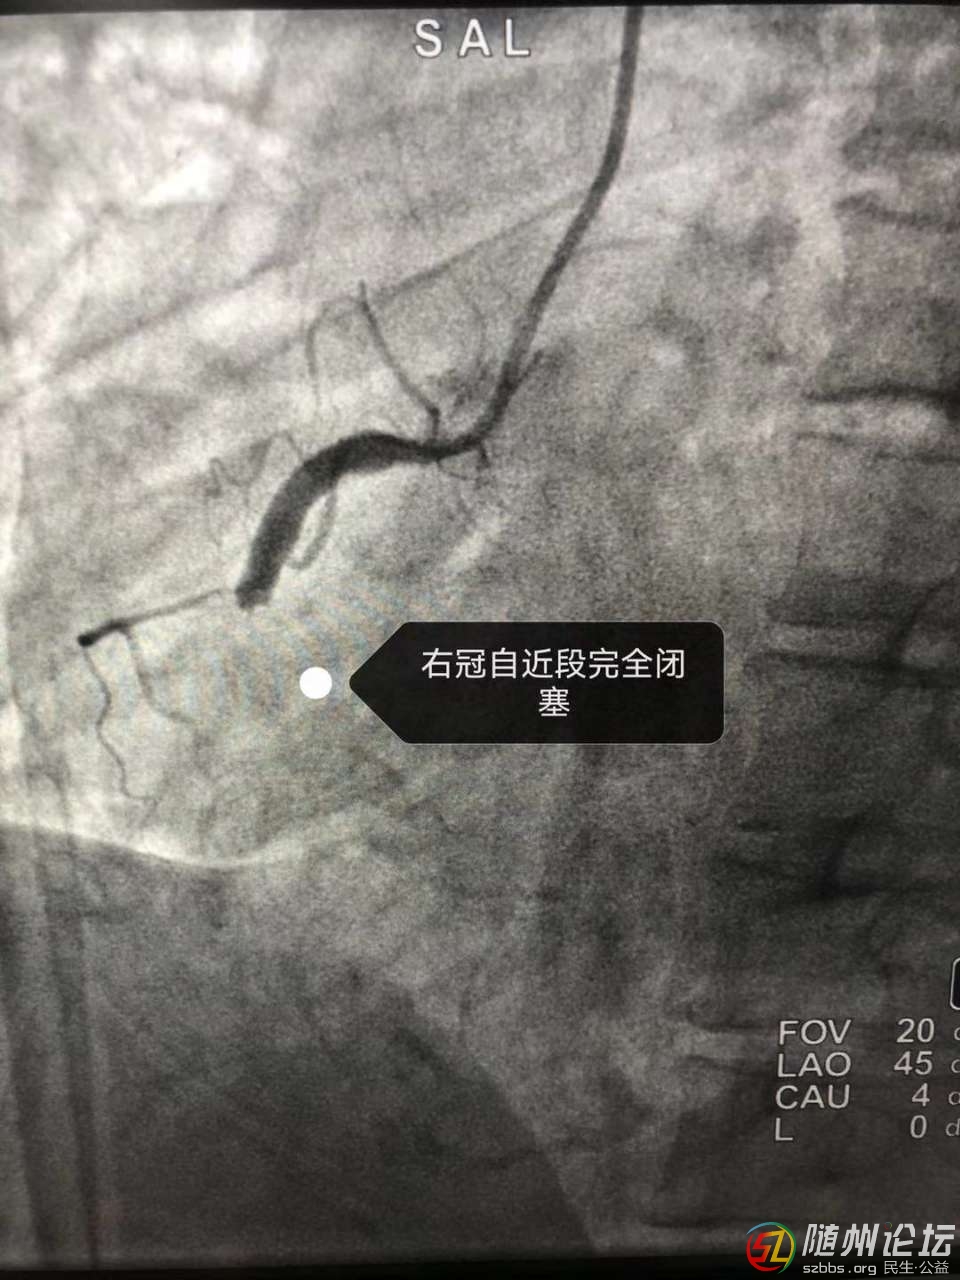

近日,隨縣中醫(yī)醫(yī)院上演了一場“生死時速”,成功救治1例急性心肌梗死患者,患者黃女士,46歲,在上班途中突發(fā)胸痛、胸悶、失語、持續(xù)不緩解,周圍人員撥打120后急診科出診 ...